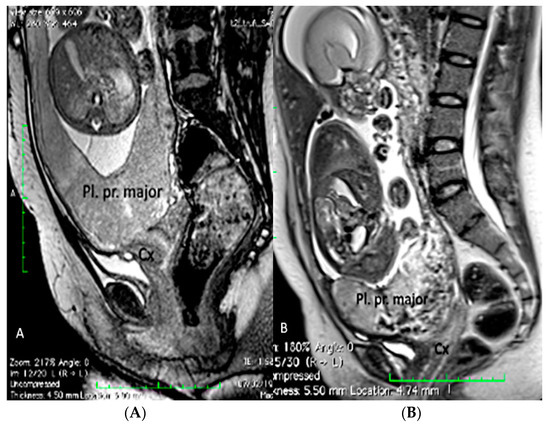

3.1.2. Placenta Praevia

- Romeo, V.; Verde, F.; Sarno, L.; Migliorini, S.; Petretta, M.; Mainenti, P.P.; D’Armiento, M.; Guida, M.; Brunetti, A.; Maurea, S. Prediction of placenta accreta spectrum in patients with placenta previa using clinical risk factors, ultrasound and magnetic resonance imaging findings. Radiol. Med. 2021, 9, 1216–1225. [Google Scholar] [CrossRef]

- Guo, P.; Wu, Y.; Yuan, X.; Wan, Z. Clinical diagnostic value and analysis of MRI combined with ultrasound in prenatal pernicious placenta previa with placenta accreta. Ann. Palliat. Med. 2021, 10, 6753–6759. [Google Scholar] [CrossRef]